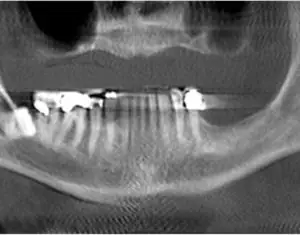

John Craig, MD, of the Henry Ford Health System is leading an international research effort to improve multidisciplinary collaboration between otolaryngologists and dental providers around